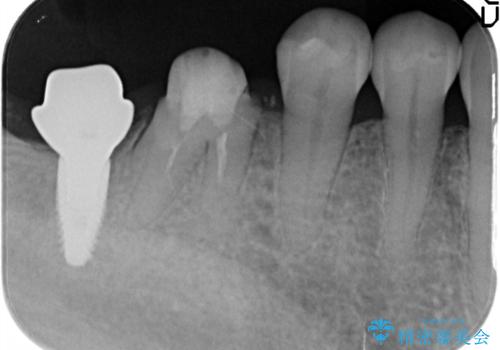

- 失った右下最後方臼歯の咬合機能の回復を求めてインプラント治療を希望され来院されました。

インプラントを埋入するのに十分な骨の量がCT検査により確認されたので、インプラントによる治療を計画します。

第二大臼歯は失ってしまうと咀嚼効率が10-30%程度低下してしまうと言われている、食事で物を噛み切るのに非常に重要な歯です。

失ってしまった奥歯をインプラントを用いて咬合機能回復することで、残っている他の歯を守ることにもなります。